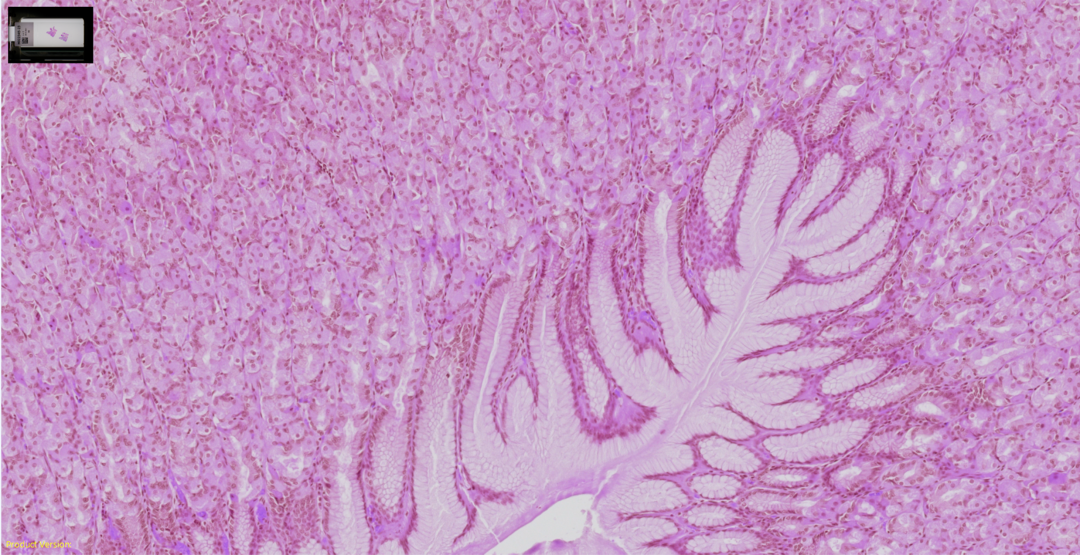

清晰捕捉各种组织和染色的细节

胃组织,H&E(苏木素和伊红)染色